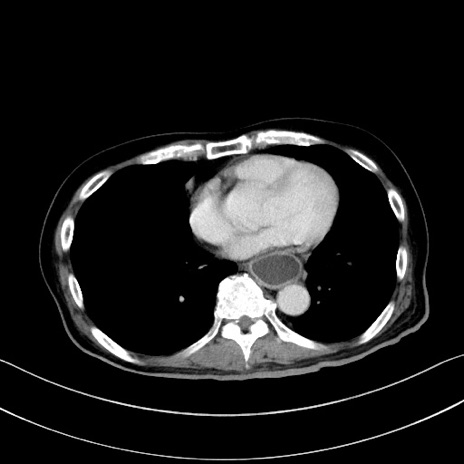

症例28(横断像)

【症例】60歳代男性

【主訴】嘔吐

【現病歴】胃癌にて胃全摘後。食思不振が悪化し、夜中に嘔吐することがある。

【既往歴】胃癌、胃全摘、脾摘、胆摘後

【データ】WBC 5900、CRP 10.56